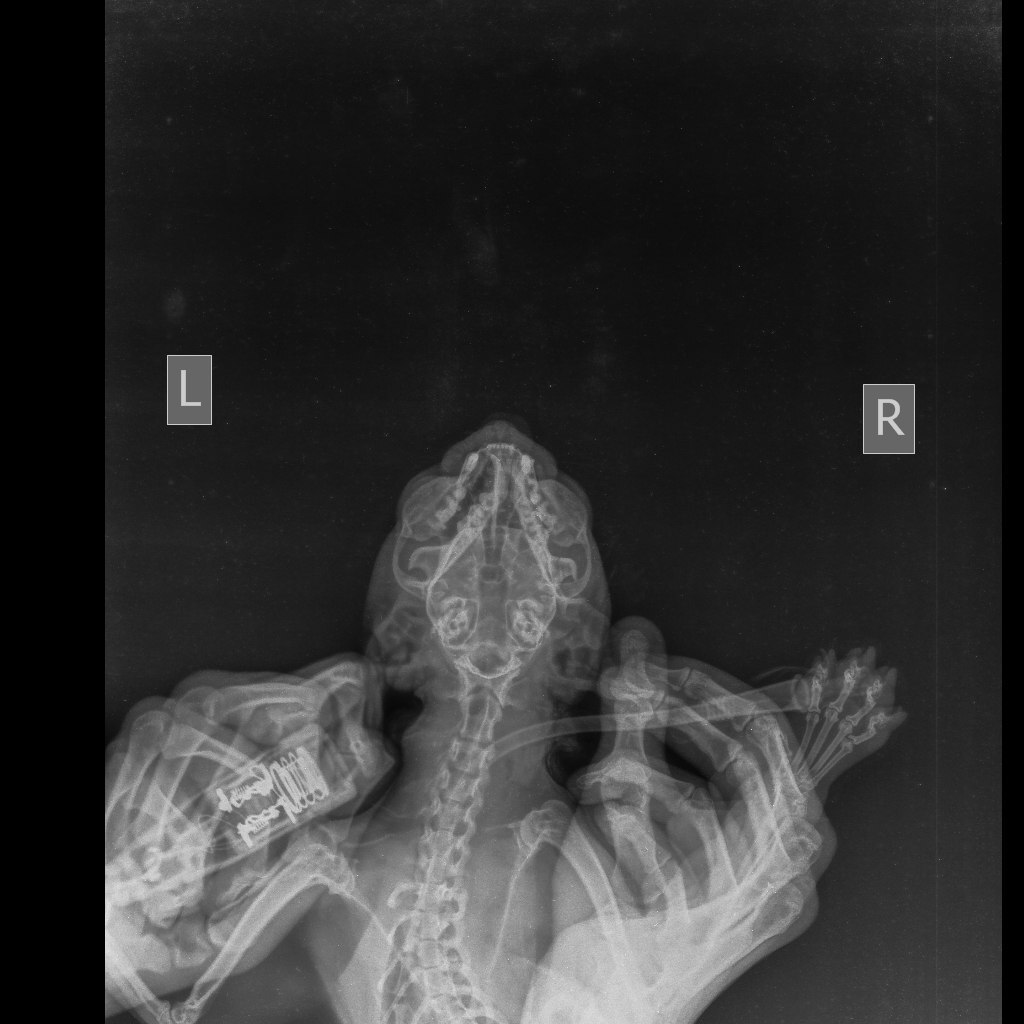

Пока кошка Милка от которой отказались ее же хозяева продолжает лежать у нас, сегодня был разговор со стоматологом.К сожалению стоматолог находится в другой клинике и не может приехать осмотреть животное, но он попросил сделать снимки записать видео, что бы предположить хотя бы какой диагноз у кошки.

После этих манипуляций был поставлен пока предварительный диагноз: Вывих височно- нижнечелюстного сустава?Перелом нижней челюсти по симфизу?

Прикладываю рентгены кошки